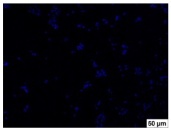

2.4. Evaluation of Macrophage Adhesion to the Surface of the Tested Samples

Following the investigation of cytotoxicity, the adhesion of macrophages to the surface of the examined samples was explored. In the experiments, it was observed that the number of adhered macrophages from the RAW 264.7 line on the surface of tablet wells without the investigated composite film materials in the microscope’s field of view was 355 ± 36 (Table 4). Upon placing RAW 264.7 cells in the tablet wells with the surface of the comparison sample “Seprafilm”, the number of adhered cells significantly decreased to 128 ± 16 within the microscope’s view field. The adhesion of macrophages on the surface of the composite film materials samples, based on the sodium salt of carboxymethylcellulose modified by allantoin (2, 3), did not differ significantly from the comparison sample “Seprafilm”.

The number of adhered cells in the microscope’s field of view was 215 ± 31 (p = 0.058) and 195 ± 29 (p = 0.064) cells, respectively. In contrast, the ability of macrophages to adhere in the samples of composite film materials based on glycoluril-modified sodium salt of carboxymethylcellulose (4, 5) was significantly lower than in sample (1) and the studied samples (2, 3). The number of adhered cells in the microscope’s field of view was 61 ± 8 and 18 ± 5, respectively.

Consequently, the tested composite film materials samples, which are based on allantoin-modified sodium salt of carboxymethylcellulose (2, 3), exhibit a diminished ability for macrophages from the RAW 264.7 line to adhere, and their adhesion value is comparable to that of sample (1).

The samples of composite film materials, derived from the glycoluril-modified sodium salt of carboxymethylcellulose (4, 5), exhibit notably reduced adhesion of RAW 264.7 line macrophages to the surface compared to both sample (1) and the examined composite film materials based on allantoin-modified sodium salt of carboxymethylcellulose (2, 3).

3.4. Adhesion of Macrophages to the Surface of the Tested Samples

Following the investigation of cytotoxicity, the adhesion of macrophages to the surface of the examined samples was scrutinized. Experimental results revealed that the number of adhered macrophages of the RAW 264.7 line on the surface of tablet wells lacking the investigated composite film materials within the microscope’s field of view was 355 ± 36 (Table 4). Upon placing RAW 264.7 cells in the wells of the tablet on the film surface of the comparison sample “Seprafilm”, the number of adhered cells significantly decreased to 128 ± 16 in the microscope’s field of view. The extent of macrophage adhesion on the surface of the samples of composite film materials based on allantoin-modified sodium salt of carboxymethylcellulose (2, 3) did not differ from sample (1), with the number of adhered cells in the microscope’s field being 215 ± 31 (p = 0.058) and 195 ± 29 (p = 0.064), respectively. The ability to adhere macrophages in the samples of composite film materials based on glycoluril-modified sodium salt of carboxymethylcellulose (4, 5) was significantly lower than in sample (1) and the studied samples (2, 3), with the number of adhered cells in the microscope’s field being 61 ± 8 and 18 ± 5, respectively.

Hence, the samples of the examined composite film materials based on allantoin-modified sodium salt of carboxymethylcellulose (2, 3) exhibit a limited ability to adhere RAW 264.7 macrophages, and their adhesion capability is not inferior to that of sample (1). In the case of samples of composite film materials based on glycoluril-modified sodium salt of carboxymethylcellulose (4, 5), the adhesion of RAW 264.7 macrophages to the surface is significantly lower compared to sample (1) and the investigated composite film materials based on allantoin-modified sodium salt of carboxymethylcellulose (2, 3).

The plates were subjected to a 24 h incubation at 37 °C in a 5% CO2 atmosphere. Following this, non-adherent cells were removed by resuspending the cell suspension. Cells attached to the surface of the composite film materials were subsequently fixed with 2.5% glutaraldehyde for 30 min and stained with fluorescent dyes, specifically Phalloidin-Atto-488 for cytoskeleton staining and DAPI for nucleus staining.

The count of cells adhered to the surface of the composite film materials within the microscope’s field of view was conducted utilizing a Leica DMi8 fluorescence microscope [40]. Three repetitions of experiments were carried out for each composite film sample and the comparison sample “Seprafilm”, with the number of adhered cells in each experiment assessed across three fields of view.